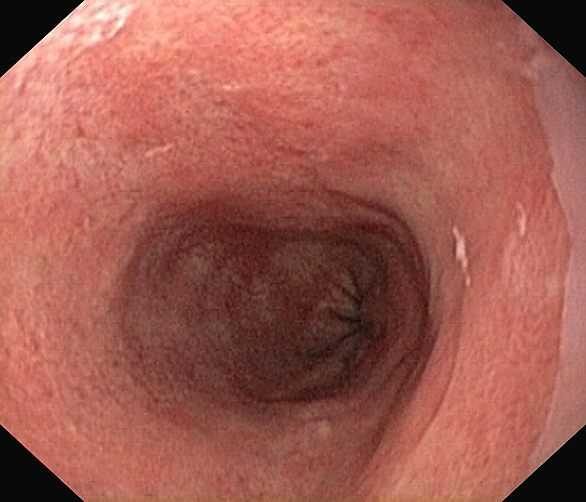

Reflux oesophagitis grade D according to the Los Angeles classification